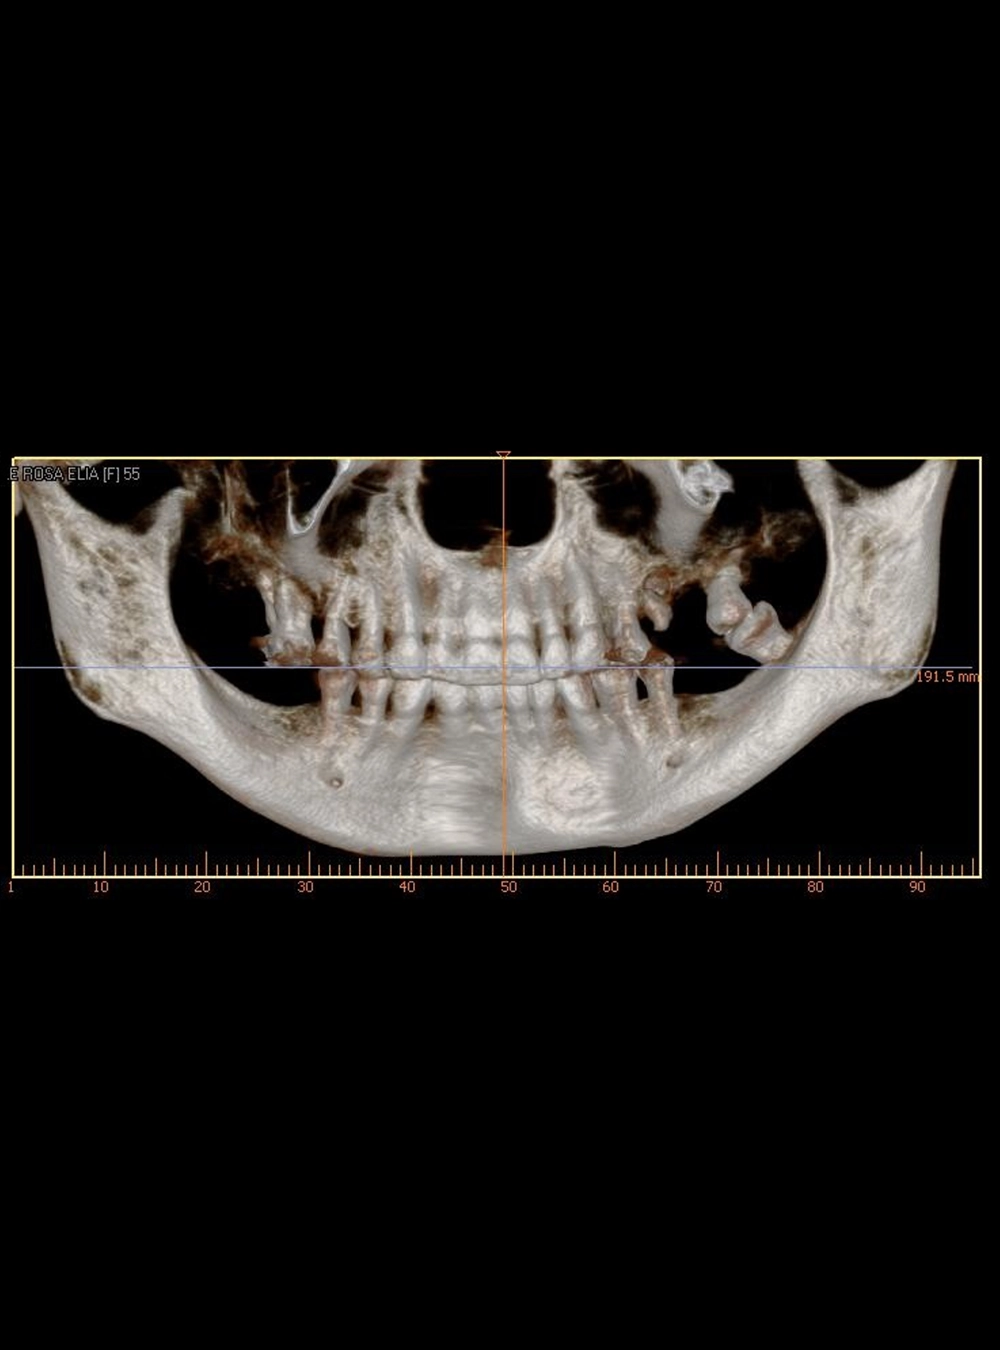

Tomografía Volumétrica

Cone Beam (USB o CD)

Dientes Retenidos - Vista RX

Dientes retenidos - Vista Tomografía

Panorámica en Tomografía Cone Beam